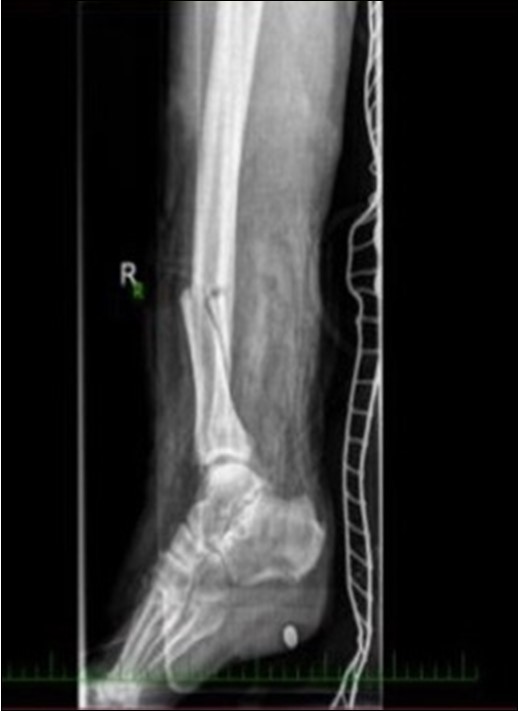

Figure 3.22 January – primary X-ray oblique splinter fracture of the tibia shaft

Figure 4.Debriteman and removal of macroscopic impurities Fracture stabilization using external fixator Reconstruction of soft tissue, subcutis and skin, necrectomy Installation of flushing lavage Covering defects with artificial skin – Syncryt

Figure 5.22 January – primary X-ray - Fracture stabilization using external fixator

Figure 6.22 January – primary X-ray - Fracture stabilization using external fixator